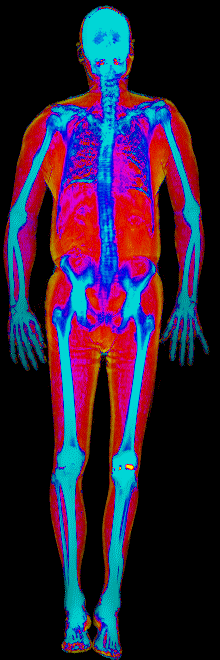

A DEXA scan passes two low-dose X-ray beams through your entire body, head to toe. Different tissues absorb different amounts of energy: bone absorbs the most, muscle and lean tissue less, and fat the least. The scanner reads how much energy made it through every pixel and assigns each one to a tissue type.

The colorful image at the top of every BodyStats DEXA report is literally that map. Bone shows up in cyan and white. Lean tissue is red. Fat is yellow and orange. Your body-fat percentage isn’t an inference — it’s a count of how much of that image is yellow and orange, broken out region by region: left arm vs right, left leg vs right, trunk, android (belly), gynoid (hips). And visceral fat — the dangerous abdominal fat that bioimpedance can’t see at all — comes back as its own number in cm².

This page features real, anonymized DEXA scan images from BodyStats clients, organized by gender and body fat percentage in 5% increments. DEXA (Dual-Energy X-ray Absorptiometry) is the clinical gold standard for measuring body composition — far more accurate than scales, calipers, or visual estimates.

Each colorized scan shows the distribution of fat tissue (shown in warmer colors) and lean tissue (cooler colors) throughout the body. Compare your own DEXA scan to others in your range, or see what different body fat levels actually look like on a scan.

Male DEXA Scans by Body Fat %

10 to 15% body fat